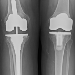

Most Popular Surgery Thanks to Obamacare: Knee Replacements

A report from the Society of Actuaries shows that the most popular “preference-sensitive” procedure undergone by new Obamacare subscribers is knee replacement surgery. A preference-sensitive procedure is one without which a patient can continue for some time, although their quality of life can be improved with the operation. read more